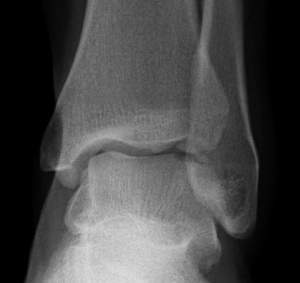

Xray

Stage II medial osteochondral fragments

Stage III medial osteochondral fragments

Stage IV anterolateral osteochondral fragment